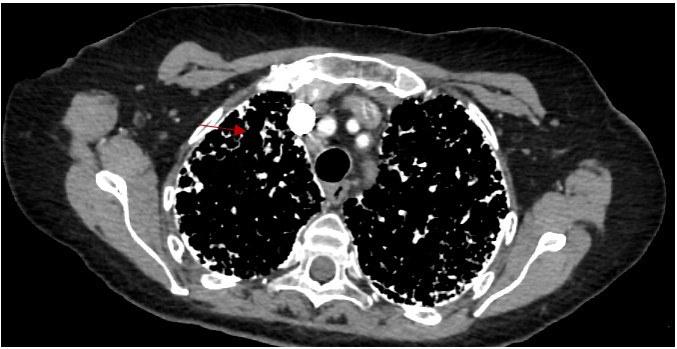

A 65-year-old non-smoking Caucasian female presented with 2-years of progressively worsening dyspnea and dry cough. She denied any history of malignancy, sick contacts, pets, or significant exposures. On physical examination, she was noted to have scattered crackles. Sputum culture and viral respiratory panel were negative, and autoimmune serology workup, including ANA, RF, MPO, PR-3, Anti-CCP, C-ANCA, P-ANCA, and anti-Scl-70, were within normal limits. Chest x ray, CT chest revealed the below findings (Figure 1):